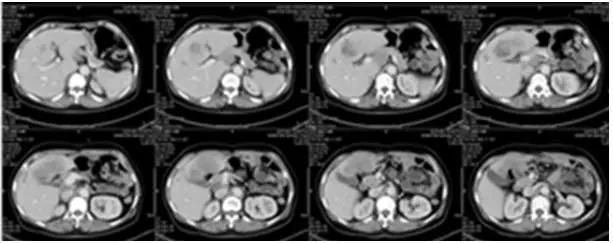

2016年1月至2月,患者开始接受阿帕替尼425mg+伊立替康0.24g d1q3w的三线治疗共2个疗程。2016年3月1日疗效评估为SD,肝左叶及尾状叶低密度影,较前增大17%。从2016年3月起,将剂量调整为阿帕替尼加量至850mg +伊立替康0.24g d1 q3w,又接受了2个疗程的治疗。

图6 2016年3月1日CT